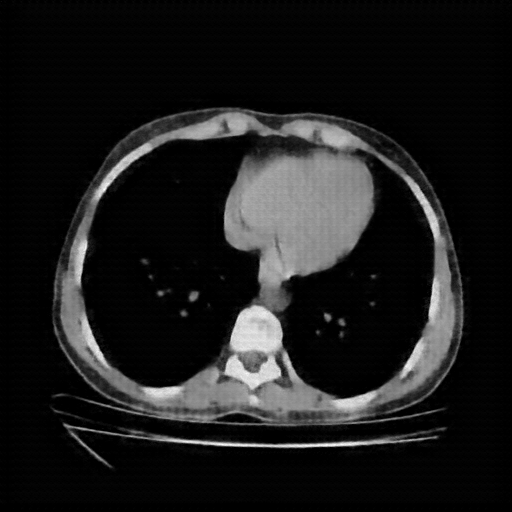

Original NATIVE CT scan (input)

Full window (WL 1023.5, WW 4095 β†’ Low βˆ’1024, High +3071)

Actual HU range: [-160.0, 240.0]